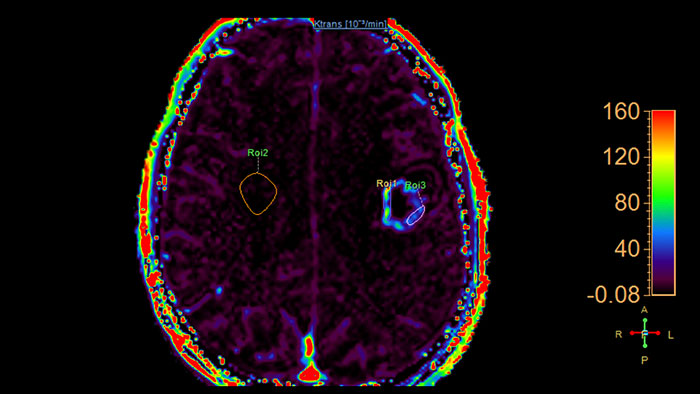

Lesion characterization by reviewing vascular leakage

Designed to visualize T1 weighted DCE 3D datasets and assist in analyzing the tissue response.